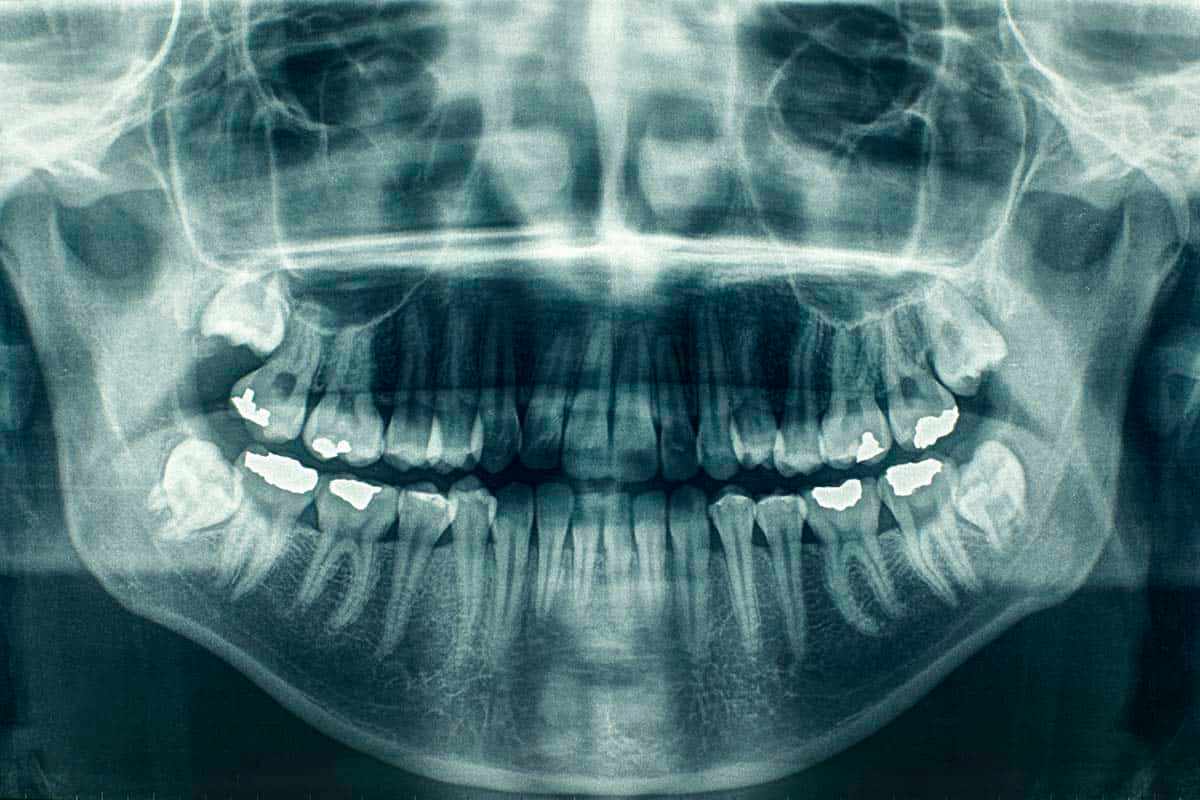

Radiografía Panorámica

La radiografía panorámica proporciona una vista completa de toda la boca en una sola imagen. Es esencial para:

• Planificación de tratamientos ortodónticos

• Evaluación de dientes incluidos

• Diagnóstico de problemas de ATM

• Detección de quistes y tumores